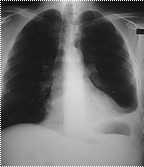

При ендобронхіальному

рості пухлина поступово звужує просвіт бронху, що викликає недостатність

надходження повітря в відповідний сегмент легені і виникненню в ньому

гіповентиляції. Ця ділянка на фоні повітряної легені стає менш прозора, що

краще проявляється на вдиху при рентгеноскопії. При подальшому рості пухлини

виникає клапанна емфізема, яка рентгенологічно краще проявляється на видиху

збідненням судинного рисунка. Коли просвіт бронху повністю перекривається

пухлиною розвивається ателектаз з оточуючим його запаленням (рис.1,2,3).

Справа в тому, що

в ділянці легені, яка спалася, дія еластичної тяги приводить до розширення

невеликих бронхів, артерій, вен та капілярів, що викликає збільшення

кровонаповнення. Тому рано чи пізно в зоні ателектазу виникає запалення

(рис.4). Враховуючи неспецифічність рентгенологічного зображення центрального